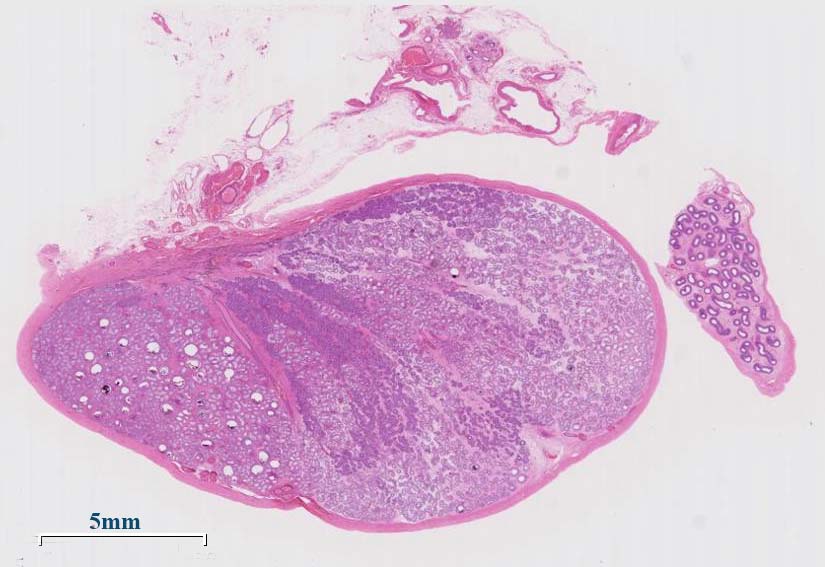

症例 16歳男性

生下時より陰嚢内に左睾丸がなかったことに気づかなかった。CT, MRIで上前腸骨棘の高さで左腸腰筋前面に睾丸と思われる3cmの腫瘤を認めた。左腹腔内精巣摘出術を施行。悪性腫瘍の有無, 造精機能を調べた。

摘出左睾丸肉眼所見

Cryptorchidism停留睾丸

停留睾丸は正常位置の睾丸よりも30-50倍の頻度で悪性腫瘍を合併する。